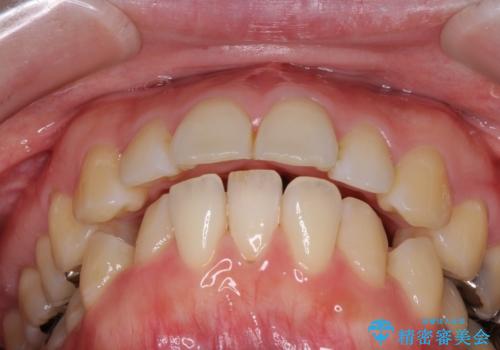

口が閉じずらく、口元出てるのが気になる ワイヤー抜歯矯正による口元の改善

- 口が閉じずらく、口元が突出している状態でした。

上下左右の歯を1本ずつ、合計4本抜歯して、ワイヤーにて矯正することとなりました。

もともと下の前歯の永久歯が1本欠損しており、抜歯部位の選択を考慮しなければならない症例でした。シミュレーションを事前に行い、下顎の抜歯部位を決定しました。